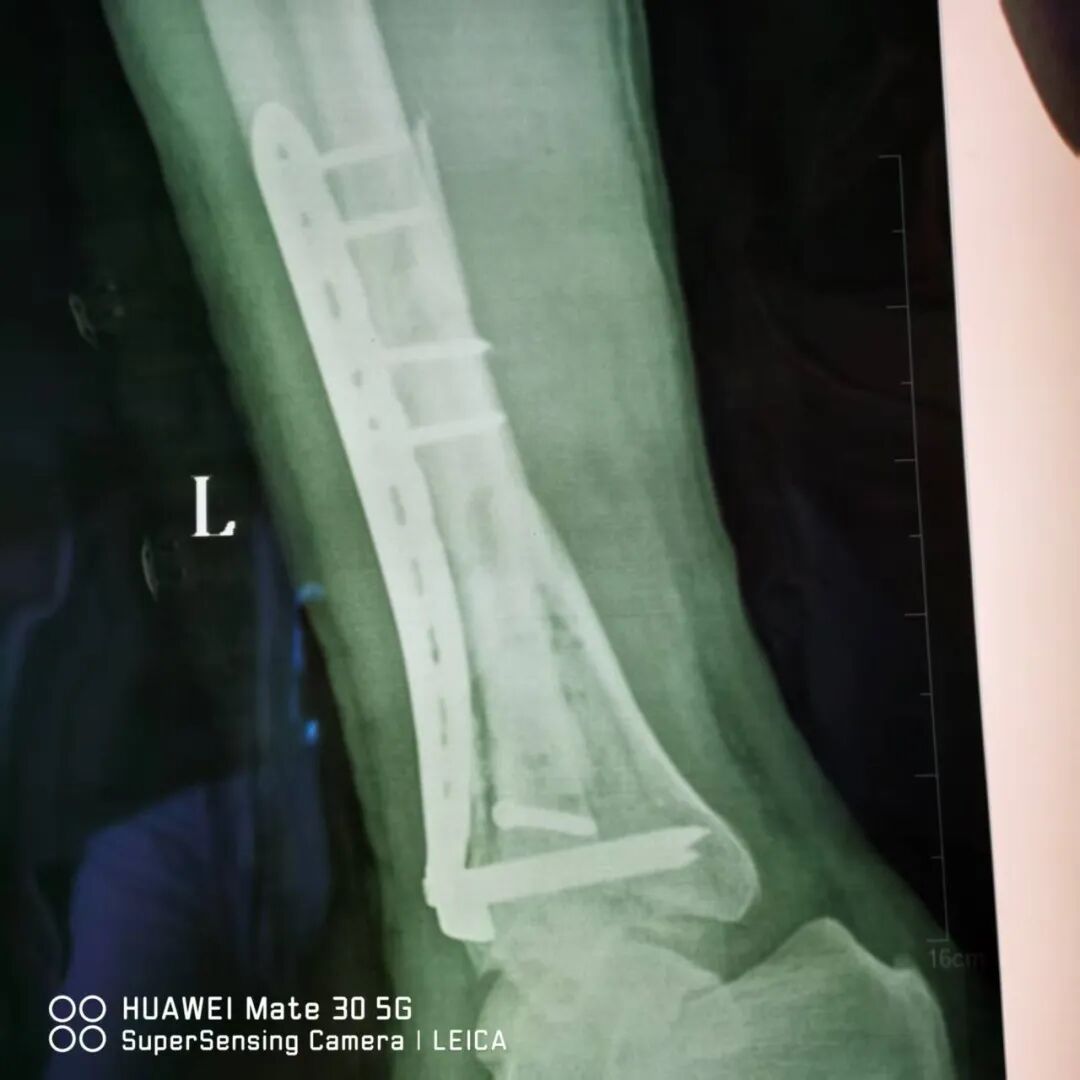

近日,阳光医院骨科成功为一名严重踝部摔伤患者分期实施手术。通过分阶段治疗策略有效解决复杂伤情,为患者康复奠定坚实基础。 患者赵XX在给房子换石棉瓦不慎摔下来,当时左小腿疼痛并流血,不能活动,伤口内骨折端外露,家人紧急将他送至阳光医院救治。 01 左踝关节骨折(Pilon骨折,AO分型C3) 经急诊摄片检查示:患者左胫骨远端粉碎性骨折,左腓骨中下段骨折(Pilon骨折,AO分型C3),同时伴有大面积皮肤软组织坏死及血管神经损伤,若直接进行骨折复位固定,感染风险极高且不利于伤口愈合。因骨折情况复杂,手术难度较大,我院骨科团队迅速组织多学科会诊,结合患者伤情特点,制定“清创维稳-骨折复位固定”的分期手术方案。 02 分期手术 第一阶段(急诊期),骨科团队优先对创面进行彻底清创,清除坏死组织并妥善处理血管神经损伤,鉴于开放性骨折创面污染重、感染风险高,同期行左胫腓骨骨折复位外固定架固定手术。术后予积极抗感染、对症治疗及精心护理,在医疗团队及家人支持配合下,伤口愈合良好。 第二阶段(二期手术内固定,一期术后2周),待软组织条件稳定后,骨科团队为患者行切开复位L型锁定钛板内固定术,术中同期取同侧髂骨行自体骨移植,术前术后均行影像学检查学评估。两次手术方案合理,衔接紧密,团队配合良好,术中实现骨折部位精准复位与可靠固定,治疗顺利完成。 术 后 目前,患者伤口愈合良好,骨折部位稳定性显著提升,已进入系统康复训练阶段。骨科主任董庆武表示:“分期手术策略可最大程度降低严重创伤的并发症风险,保障手术安全性与治疗效果。此次成功治疗展现了我院在复杂创伤救治领域的综合实力,也为同类病例提供了宝贵经验。”